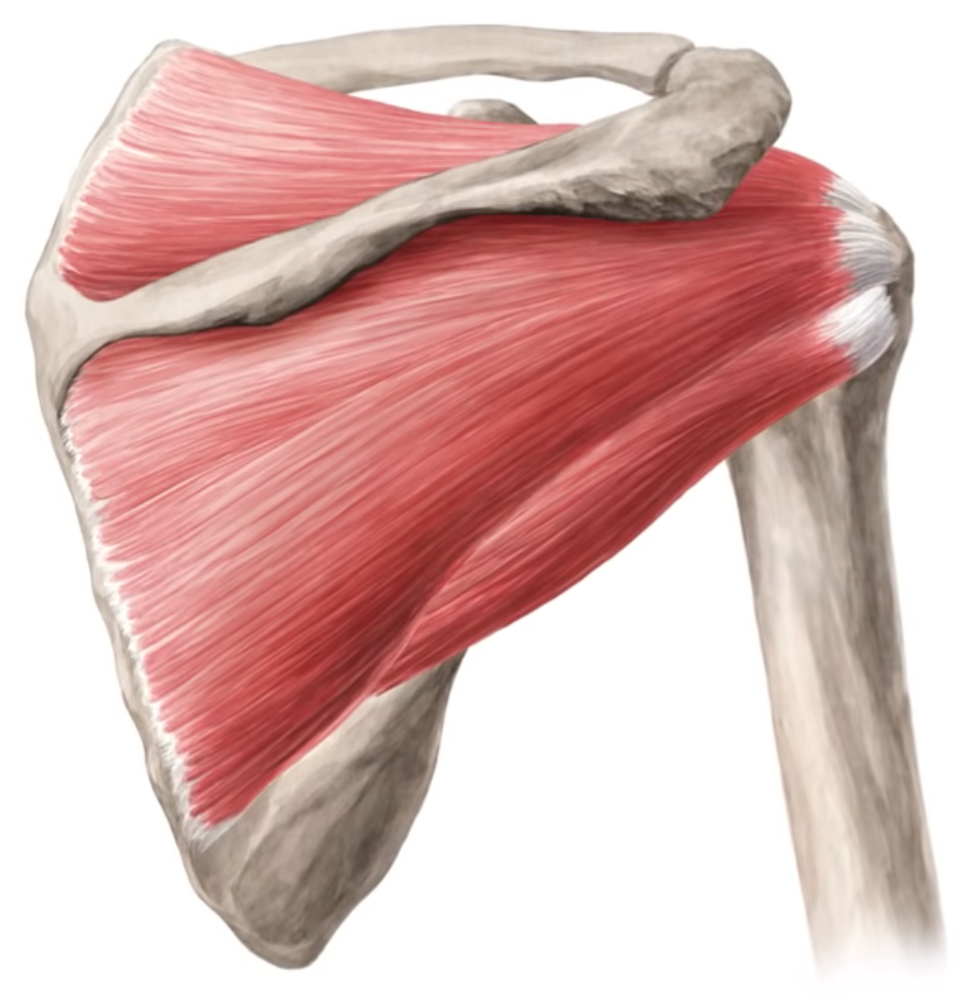

Фотографии мышц ротаторной манжеты плеча